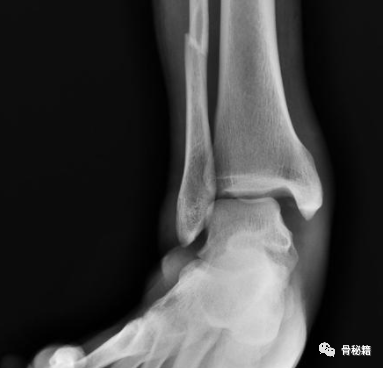

它的发生是由于外翻和/或旋前损伤,或者可能与外踝骨折有关。

三角韧带通常从其胫骨附着处撕脱,导致距骨外侧移位,内侧间隙增加(> 4 mm)。